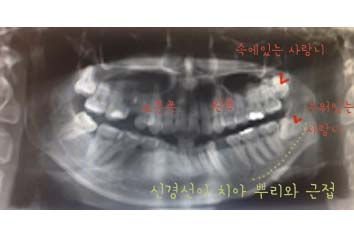

현재 상태로는 오른쪽 하악 사랑니만 나있는 상태였고 나머지는 잇몸속에 꽁꽁 숨어있는 상태였습니다.

하악 사랑니의 뿌리가 깊어 턱 라인을 따라 나있는 신경과 겹쳐있는 상태였고 이 사랑니를 잘못 뽑으면 짧으면 몇주 혹은 몇달, 평생을

아랫입술및 턱 피부의 감각이 무뎌지거나 없을수있다며 조금은 무서운 말씀을해주셨어요.. 이부분때문에 발치전 저는 CT를 찍기로

하였습니다.

그중 왼쪽 하악 사랑니는 누워서 앞니를 미는 모습으로 위치하였고 상학의 양 사랑니는 잇몸 깊숙히 자리잡고있었습니다.